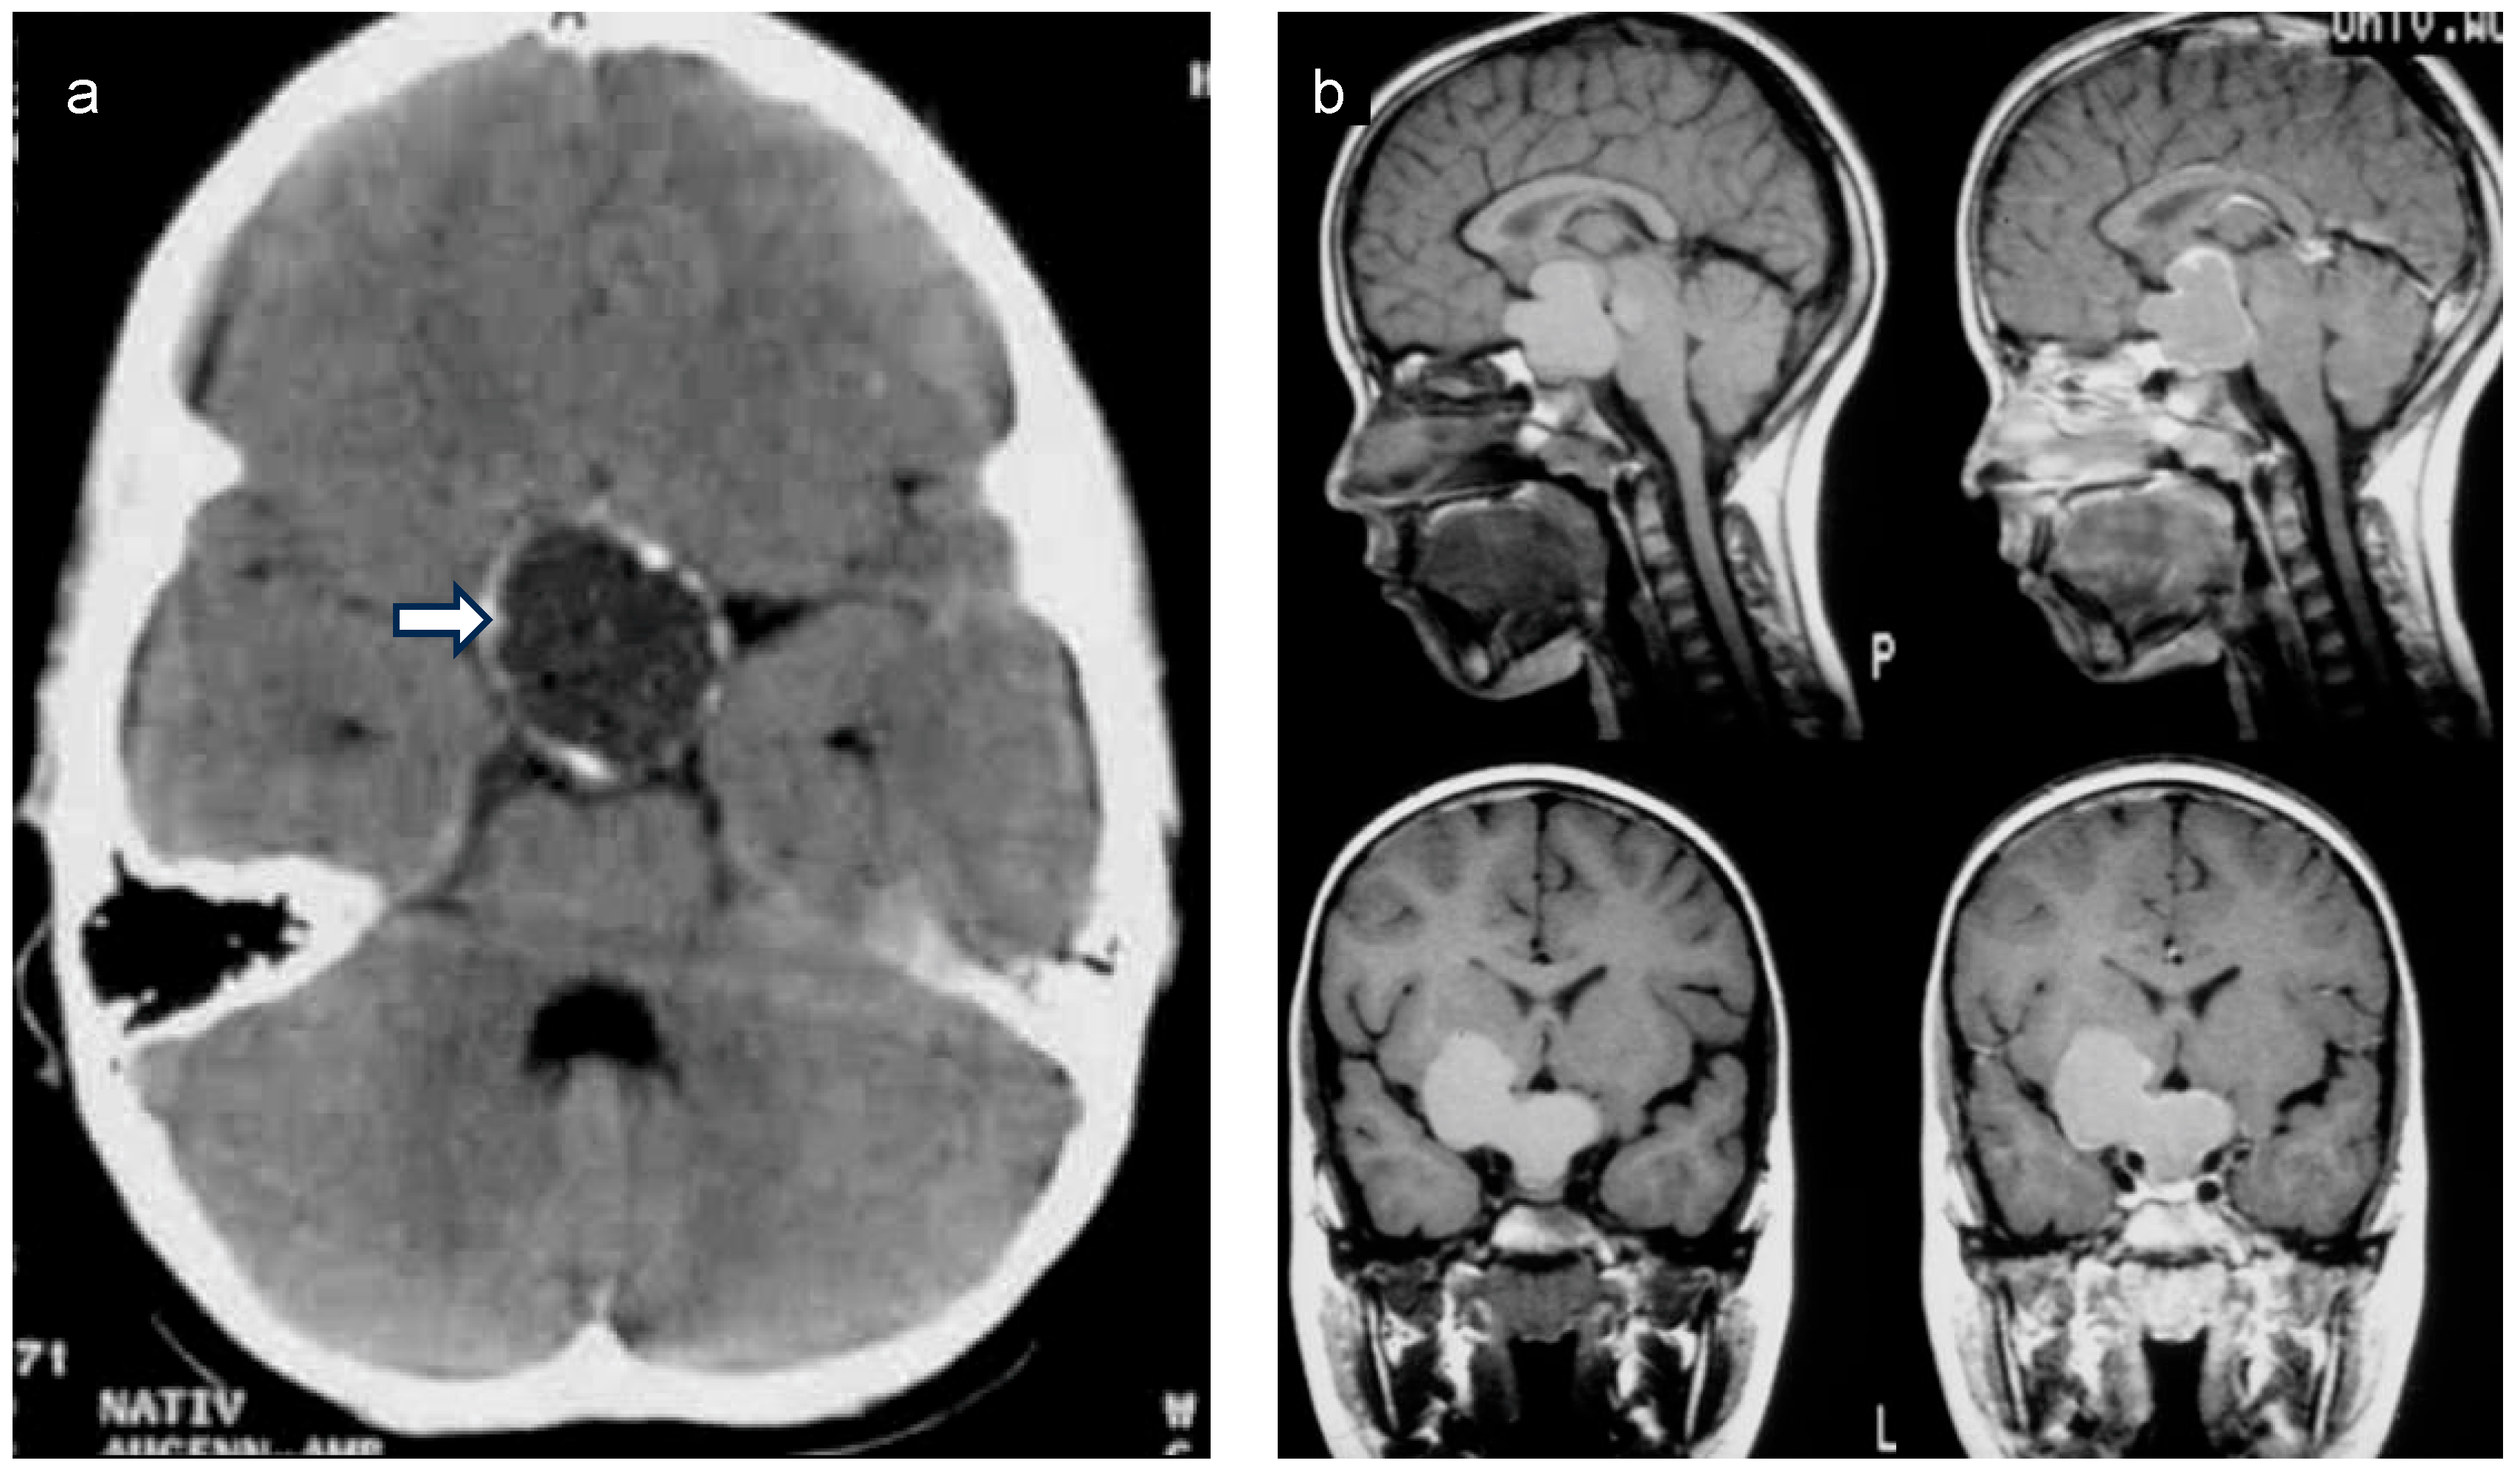

Children diagnosed with CP have a median age of 5 to 12 years old and present with varied initial symptoms and complaints. Headache, stunted growth, polyuria/polydipsia, and visual impairment can be the first signs of a CP during childhood and adolescence [9,10]. When CP is suspected, patients should ideally undergo comprehensive whole-brain magnetic resonance imaging (MRI), assessing the sellar and suprasellar area (Figure 3) via 3D high-resolution coronal, axial, and sagittal T2-weighted images and volumetric T1-weighted sequences. For initial MRI scans of CPs, using an intravenous contrast agent is recommended. To guide diagnosis, MRI should be supplemented with computed tomography (CT) scans (limited sellar scans sparing the lenses, without an intravenous contrast agent) to visualize calcifications. After neurosurgical intervention, an MRI scan within 4 weeks serves as the initial postoperative imaging method for assessing the degree of surgical resection [11]. Typically, CP is located at a single central nervous system location, being unifocal and often having solid and cystic tumor components [12]. Rare cases of ectopic CP have been reported [13].

Figure 3.

(a) Native coronal computed tomography (CT) of the skull of a patient with childhood-onset craniopharyngioma, depicting calcifications in the cyst membrane of a craniopharyngioma (arrow). (b) Sagittal and frontal magnetic resonance imaging (MRI) of a patient with childhood-onset craniopharyngioma. Both patients were recruited in the KRANIOPHARYNGEOM 2007 trial.